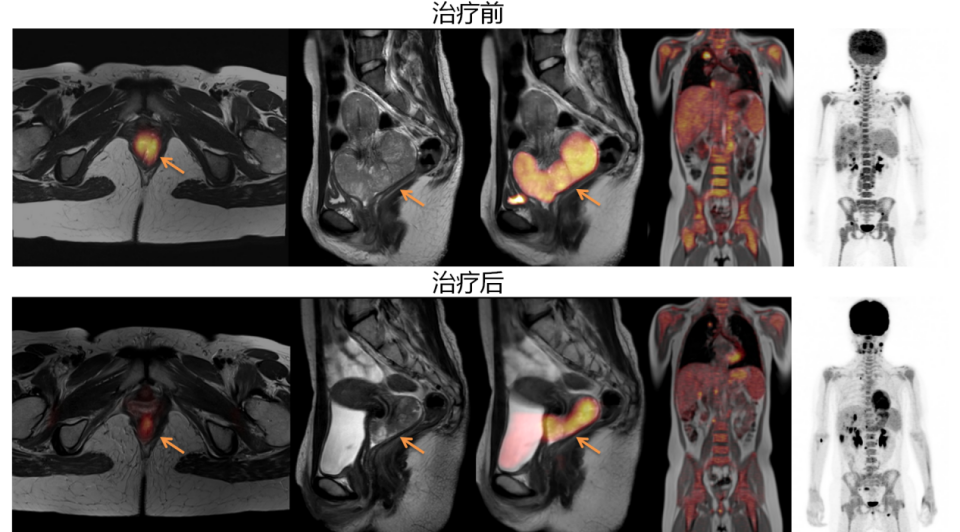

对于肿瘤的早期发现、精确分期、疗效评估及术后监测,PET-MR表现卓越。它不仅能清晰显示肿瘤的形态、位置,更能从代谢水平揭示其活性,为肿瘤的“精准化”治疗提供关键依据。

▲60岁女患者,宫颈癌多发转移化疗前后疗效评价